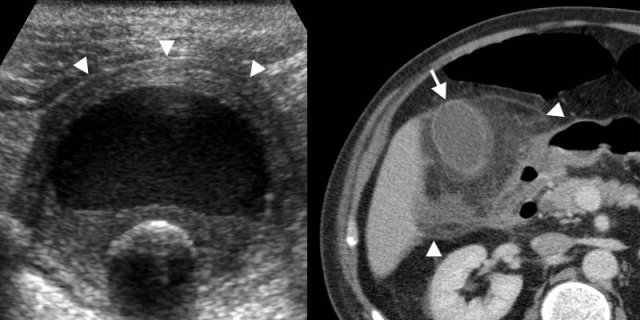

On the left images of a 62-year-old man with acute calculous cholecystitis.

Transverse sonogram at the spot of maximum tenderness shows a non-compressible hydropically distended thick-walled gallbladder (arrowheads), with an intraluminal stone and sludge or debris.

Contrast-enhanced CT depicts extensive fat inflammation (arrowheads) surrounding the

gallbladder (arrow).